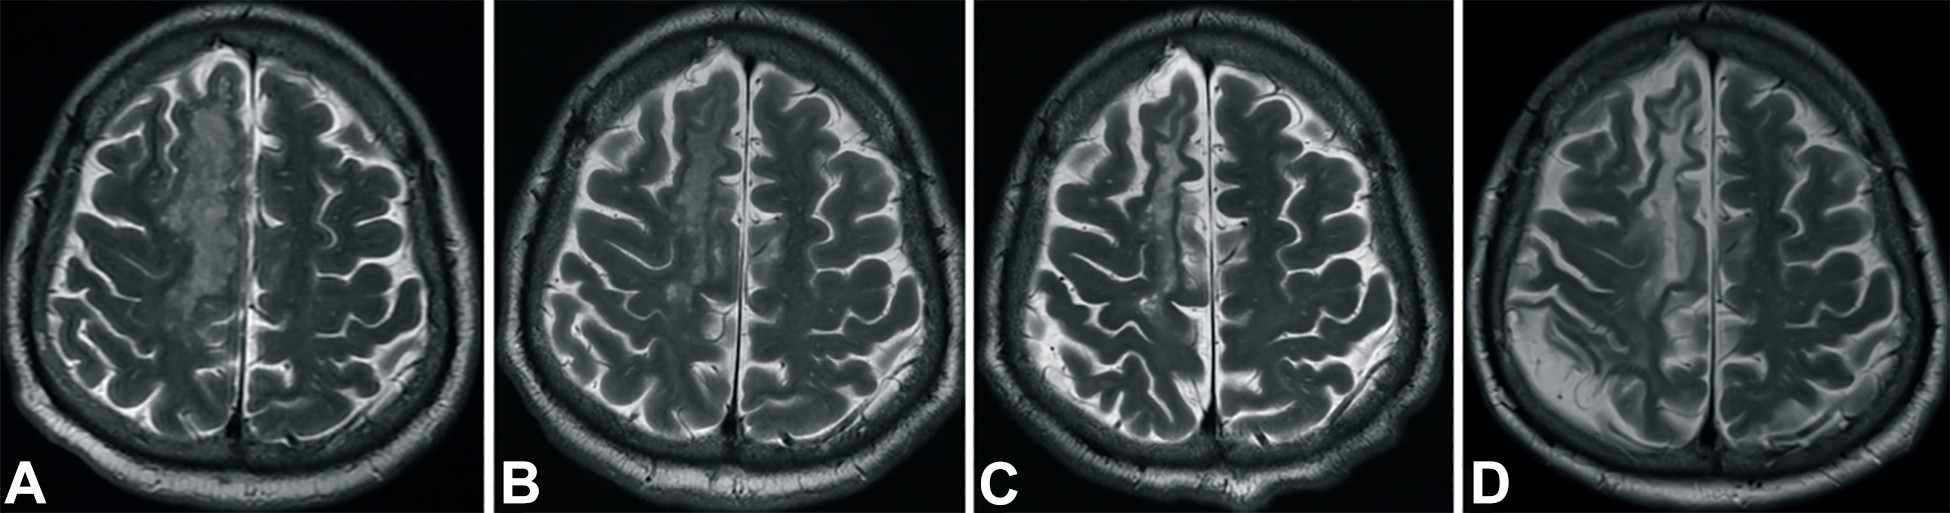

發(fā)病后2小時和8天行彌散加權(quán)成像(DWI)檢查,發(fā)現(xiàn)右側(cè)放射冠梗塞(白色信號增加),3個月后梗塞散在,6個月后消失(圖2A-D)。

梗塞發(fā)生后2小時、8 天、3 個月和 6個月獲得的T2加權(quán)圖像顯示右側(cè)放射冠白色強度增加(圖3A-D)。